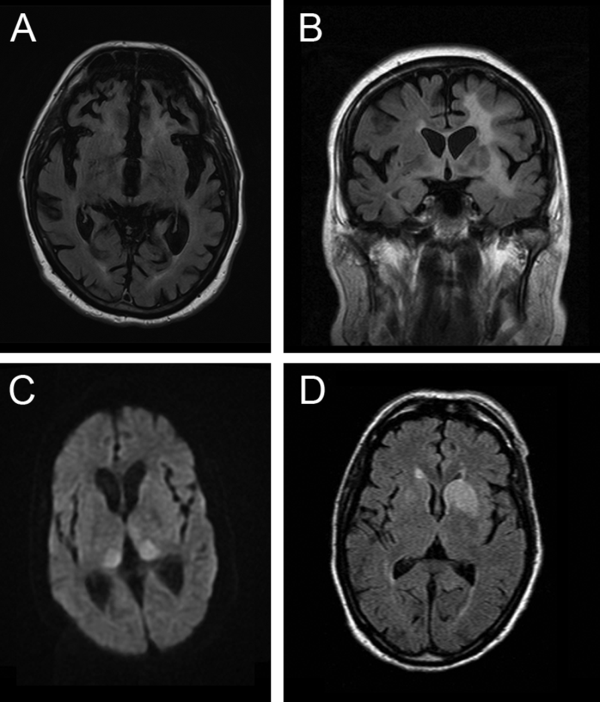

N-methyl-D-aspartate receptor (NMDAR) antibody encephalitis is the most commonly recognised type, initially linked to ovarian teratoma in young women, which remains a prompt to consider the diagnosis. Like in patients with CJD, the history often includes a non-specific prodromal stage, developing into behavioural and psychiatric features, and early generalised and focal seizures that would be very unusual in CJD. Movement disorders commonly develop in CJD, but the specific facial dyskinesia of NMDAR encephalitis would prioritise the disorder. Other flags for the disorder are a CSF pleocytosis, CSF oligoclonal bands, and MR imaging findings (Table 3). These can include T2 or FLAIR hyperintensity of the striatum, thalamus and cortex as might occur in CJD (figure 3) but more typically include abnormalities in other areas, particularly the mesial temporal lobe and hippocampus, and also the brainstem, cerebellum and white matter, often with enhancement or mass effect from inflammation. We recommend testing at least serum in all patients suspected to have CJD and CSF in patients with flags for the disorder.

Figure 3

MR scan of brain in four patients presenting as mimics of prion disease. (A) C9orf72 mutation showing severe generalised atrophy with no parenchymal abnormal signal. Severe atrophy does occur late in some cases of Creutzfeldt-Jakob disease (CJD), but usually diffusion-weighted sequences reveal restricted diffusion. (B) B-cell lymphoma confined at the time of presentation to the brain. Note the extensive white-matter signal change with the normal cortex. Occasionally, the leukoencephalopathic form of CJD has white-matter signal alteration, but this is associated with grey matter destruction. (C) N-methyl-D-aspartate antibody encephalitis with MR imaging showing the pulvinar sign. This sign develops in most cases of variant CJD and has rarely been described with other pathologies. (D) Voltage-gated potassium channel (Casp-1) antibody encephalitis showing unilateral basal ganglia high signal on diffusion-weighted imaging but not on the apparent diffusion coefficient map (scan not shown). Note that the swelling of the caudate is a feature that does not occur in CJD.

Voltage-gated potassium channel (VGKC) complex antibody encephalitis is similarly a crucial mimic of CJD to exclude. Importantly, we now know that pathogenic antibodies are directed at individual members of the VGKC multiprotein complex, for example, LGI1, which may give more specific tests. While associated with a wide range of clinical syndromes, the most commonly confused picture with CJD is one that may include both peripheral manifestations—neuromyotonia, a twitching or stiffness related to spontaneous motor nerve excitability, and autonomic disturbances—and central manifestations, such as brief and frequent seizures affecting ipsilateral face and arm (termed ‘faciobrachial dystonic’), insomnia, memory impairment and behavioural disturbances or more florid manifestations of an encephalitis. Investigation prompts to the diagnosis include hyponatraemia and MR imaging abnormalities of the mesial temporal lobe and hippocampus, which can also involve the basal ganglia (figure 3).